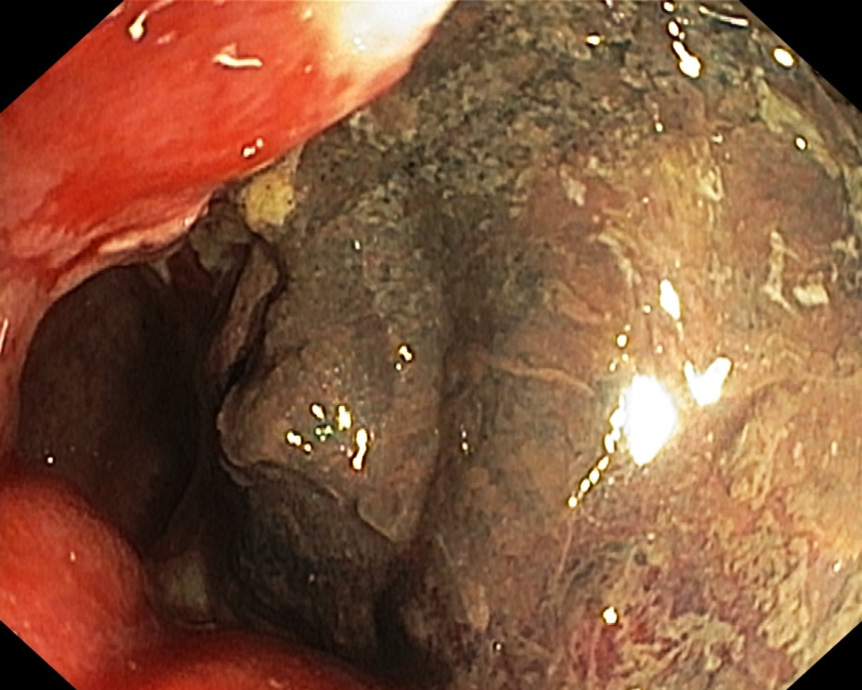

Рис. 3. Коагуляционный некроз, вкрапления гематина (02.12.2019)

Рис. 4. Некротизированные массы по передней стенке прямой кишки (13.12.2019)

После выполнения процедуры самочувствие пациента улучшилось, примесь крови при дефекации практически исчезла. 02.12.2019 пациенту выполнен 2-й этап лечения: в нижнеампулярном отделе прямой кишки определяются множественные ангиэктазии диаметром 2−5 мм, местами сливающиеся, единичные контактно кровоточат. Определяется коагуляционный некроз (аргоноплазменная коагуляция от 25.11.2019), под фибрином вкрапления гематина размером около 2,0 × 1,5 см (рис. 3). Выполнена аргоноплазменная коагуляция крупных и сливных ангиэктазий по всем стенкам.

Через неделю после второй процедуры аргоноплазменной коагуляции пациента начали беспокоить абдоминальный болевой синдром, боли в области заднего прохода, появилась примесь крови в стуле. При контрольном эндоскопическом исследовании по передней стенке прямой кишки выявлены некротизированные массы (рис. 4). При магнитно-резонансной томографии малого таза стенки прямой кишки диффузно утолщены с сужением просвета кишки, реактивным отёком мезоректальной клетчатки; на расстоянии 4,3 см от анального края передняя стенка кишки изъязвлена на протяжении 2,3 см; на уровне изъязвления на 12−13 часах веретеновидный затёк диаметром 10 × 15 мм протяжённостью 45 мм, распространяющийся в воспалительном инфильтрате вдоль передней стенки кишки (рис. 5), верхняя граница затёка на уровне S5; стенка сигмовидной кишки без признаков воспалительных изменений; тазовой лимфаденопатии не выявлено. Предстательная железа размерами 44 × 37 × 29 мм, объём 25 см3. Строма простаты диффузно отёчная, наружный контур простаты на 15−18 часах нечёткий, в структуре паренхимы визуализируются гипоинтенсивные частицы. Клетчатка ректопростатических углов не изменена. Семенные пузырьки симметричные, малых размеров. Мочевой пузырь умеренно наполнен, стенки циркулярно утолщены до 6−7 мм, внутренний контур повышенной трабекулярности. Тазовые сегменты